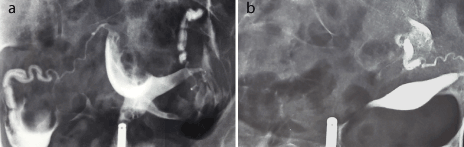

The patient’s periods were restored to normal without any inter-menstrual bleeding or dysmenorrhea. Eighteen months later she underwent a hysterosalpingography. In comparison to a preoperative exam a year before, the uterine cavity appeared very satisfactory with a smooth outline (Figures 6a-b). The left tube was patent. The right tube appeared blocked at the level of the isthmus. Hysteroscopic re-evaluation of the uterine cavity has been scheduled in the near future, when pregnancy will become desirable. Four years post-surgery she remains well and asymptomatic.

Figures 6a-b: Hysterosalpingogram showing a grossly distorted cavity before, and a normal cavity with right tubal occlusion after the procedure.